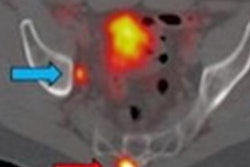

To shed more light on the topic, the researchers retrospectively looked at 388 patients with confirmed prostate cancer, all of whom underwent whole-body Ga-68 PSMA-11 PET/CT scans (Biograph 64 TruePoint or 2010 Biograph mCT 64, Siemens Healthineers) for primary staging, biochemical recurrence, or restaging from September 2017 to May 2018. Subjects received a median of 196.1 MBq (5.3 mCi) of Ga-68 PSMA-11, with a median tracer uptake period of 60 minutes.

The images detected bone metastases in 12 (13%) of 93 patients who underwent initial staging; 44 (20%) of 225 patients with biochemical recurrence; and 49 (70%) of 70 restaging patients. As expected, the incidence of bone metastases increased concurrently with rising serum PSA levels.

"Surprisingly, 38 of 216 patients (17.6%) with serum PSA levels of less than 5.0 ng/mL were found to have PSMA-positive lesions suspicious for bone metastases," the authors wrote.